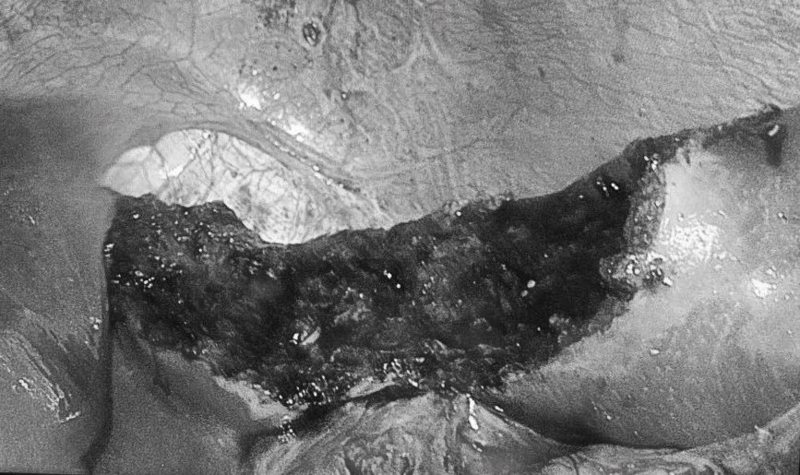

切除后创面

考虑到患者已经 反复复发脾囊肿 ,经彭兵教授/李永彬团队评估后,决定为患者实施“腹腔镜下巨大脾囊肿剥离术”,手术过程顺利并吸出囊肿内800余毫升浑浊囊液。既 治疗了脾脏本身病变, 又 避免了脾切除和部分脾切除 ,几乎不丢失正常脾脏组织,最大限度保留了正常脾脏的体积和功能,避免了脾切除术后感染、血栓和肿瘤的发生。患者术后恢复良好,在术后第2天拔除腹腔引流管,第3天顺利出院。